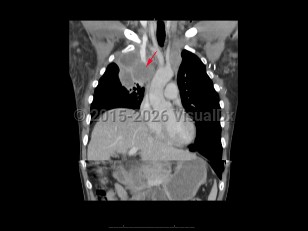

Pericardial effusionPericardial effusion